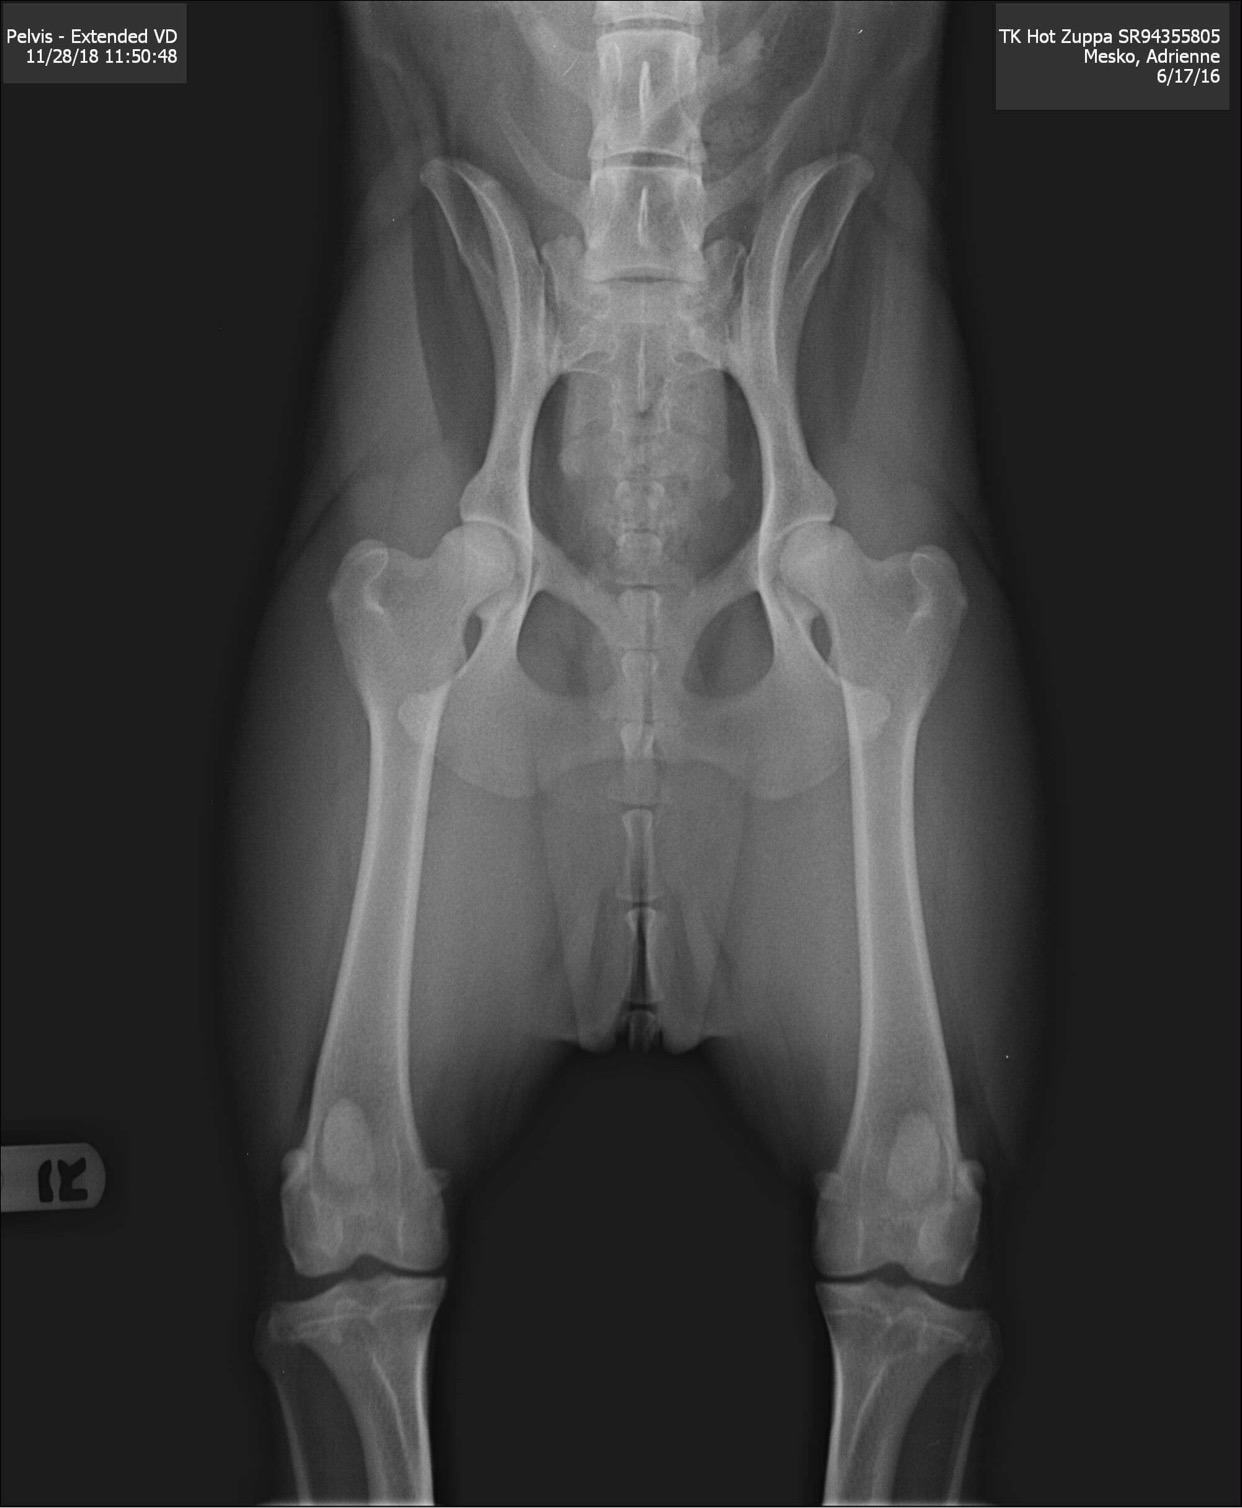

You should expect that our dogs are fully health tested for hip and elbow dysplasia, and have had their eyes examined by an ophthalmologist, and that these results are registered with the OFA (Orthopedic Foundation for Animals) for your viewing. You should also expect that all of our dogs are tested for all potential genetic conditions through DNA screening, and that those results will be made available to you upon your request. DNA screening will include testing for the dilute gene – you can expect that we breed only from dilute free lines.